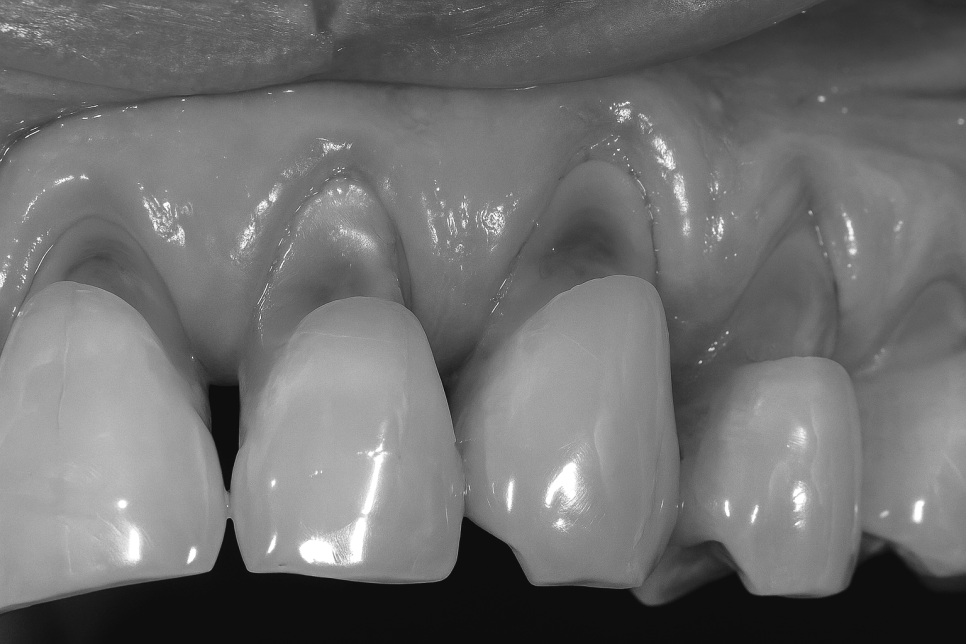

표면 에나멜이 점차 소실되어

상아질이 밖으로 드러날 수 있는데,

이곳은 에나멜보다 단단함과 내산성이

낮다는 특성을 가지고 있습니다.

이런 징후가 있음에도 계속 방치해두면

패인 홈이 더욱 깊어질 수 있습니다.

또한 이가 시린 과민증이 나타날 수 있으며,

잇몸이 점점 뒤로 후퇴하면서 치주조직을

약화시키며 치조골 손실까지도 이어질 수 있기에

그 대처는 신속할 수록 좋습니다.

그러나 그 정도가 심해 구조 손실까지

생겼을 때는 세라믹 또는 지르코니아 재료를

통한 크라운 수복이 이루어집니다.

이는 치아 전체를 덮어 보호할 수 있고

교합 기능의 회복을 돕습니다.